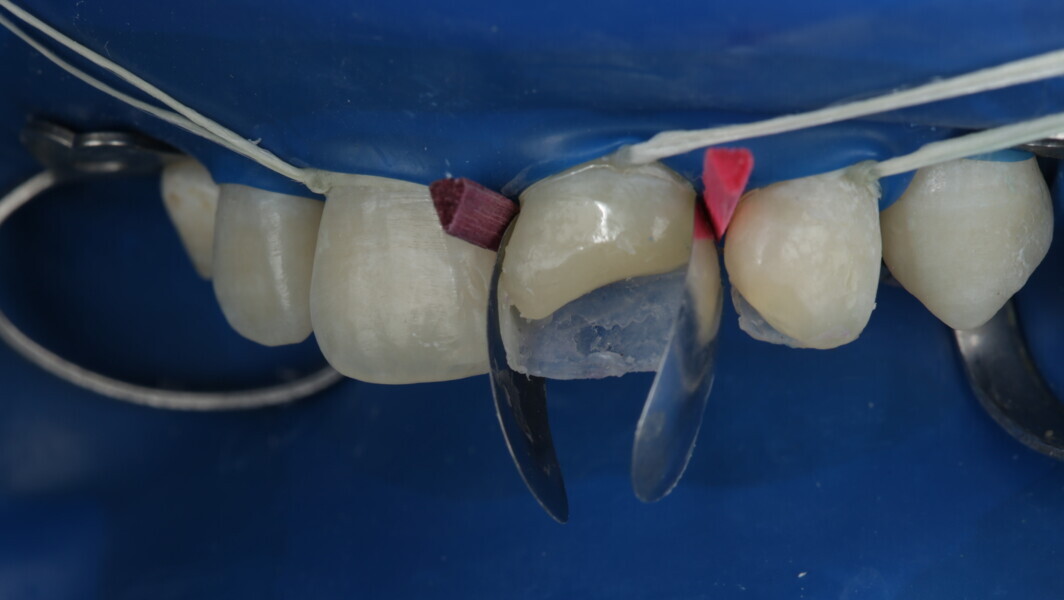

Fig 19-24: Contact build-up with band and wedge

Fig 25-30: Layering protocol step by step